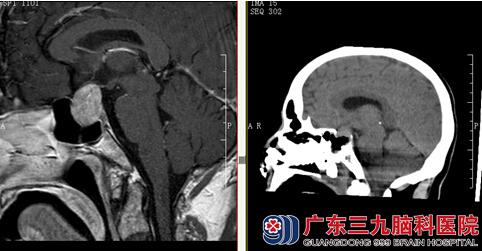

入院后予黄先生完善相关检查,查血常规、凝血、生化全套、DR胸部、心电图均未见明显异常;查头颅MRI示:鞍区占位性病变,考虑垂体瘤可能性大;向家属交代病情,需要手术,由林涛主任主刀行“经鼻蝶垂体瘤切除术”,术中肿瘤绝大部分切除。术后予预防感染、激素替代、控制尿量以及血糖、支持、对症等综合治疗,术后复查头颅CT、MRI示:呈术后改变,肿瘤基本全切除;术后病理结果回报:垂体腺瘤。术后黄先生康复良好出院。